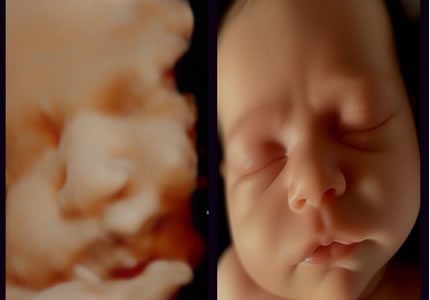

4D Bonding Experiences (24 – 34 Weeks)

Enjoy a magical glimpse of your baby’s face in real time. Ideal during 26–30 weeks when fluid and positioning are optimal.

- Utilising our advanced imaging technology, we offer you a magical window into your baby’s world. You can watch your baby’s real-time expressions, such as yawning or smiling. This session is best booked between 26–30 weeks when the baby has developed enough features for clear, detailed viewing.

- £119